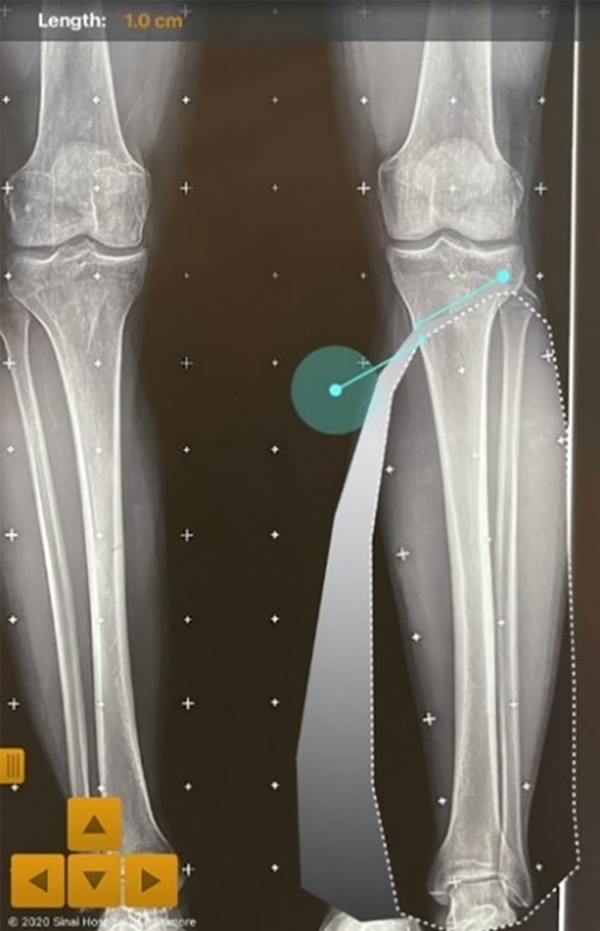

El método de planeamiento que se enumeró y explicó previamente tiene tres formas de comprobarse de forma pre e intraquirúrgica: la primera forma es mediante el software, se mide el espacio al cual se le hizo la apertura y esto da los milímetros de la cuña, que se compara con el resultado de la fórmula trigonométrica que usa la tangente del triángulo (fig. 18). La segunda forma es desarrollada por uno de los autores de este trabajo, conocido como Método Alzate, y consiste en obtener los milímetros de apertura a partir del ángulo de deformidad, al tener la longitud de osteotomía se ubica en el punto de la corrección y se mide la distancia hacia proximal, que formaría el lado de un triángulo, luego la misma medida sería el otro lado del triángulo, y se miden los milímetros del tercer lado del triángulo o su base, y esto debe corresponder al mismo resultado de la tangente del ángulo de corrección multiplicado por la distancia (fig. 19).

Figura 19: Método Alzate: En el planeamiento obtenemos la longitud de la osteotomía, y también se tiene el ángulo de corrección para que el MAD pase por el punto que previamente definimos (50% o 62%), en este caso el 50%, como sabemos que esta intersección de líneas forma el ángulo que debemos corregir, el método Alzate consiste en medir desde este punto la longitud de la osteotomía. En la imagen el punto C (Corrección), y la distancia O (Osteotomía), las medimos en cada una de las líneas, vamos a obtener dos lados de un triángulo isósceles, así que esto es la resolución gráfica de la fórmula trigonométrica. B (Brecha) sería el otro lado faltante, que corresponde a los milímetros de apertura, en este caso, 10 mm.